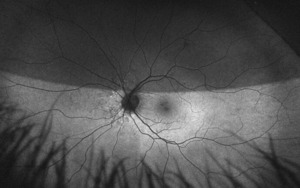

At the follow up, the patient’s vision remained stable without glasses, 20/20-1 OD and 20/25-1 OS. Humphrey Visual Field, Optos, Optos with autoflourescence, repeat B Scan, and color plates were performed at this visit. Color vision was normal in both eyes.

At the end of this visit, a diagnosis of optic nerve head drusen was determined due to the findings on the B-Scan. A highly reflective foci was seen due to the calcification present on the optic nerve head. There was no hyperflourescence seen on the fundus autoflourescent photos, but the drusen were likely buried. A 3-month follow-up was scheduled for repeat dilated fundus exam to ensure hemorrhages were resolving and no changes to the optic nerve head or visual acuity were occurring. The patient was educated on the condition of optic nerve head drusen and its effects on visual fields and vision. He was educated to return to clinic immediately if any changes were noted before the follow-up in 3 months.

On this visit, the patient’s posterior pole revealed a blurred inferior temporal neuroretinal rim in both the left and right eyes. The right eye previously had no appearance of edema in the initial visit. The discs were crowded at .10/.10 OU as noted at initial visits and no hemorrhages were seen on this examination. All other structures posteriorly were consistent with the original examination.

After additional testing was completed, and comparison of previous photos were conducted, it was determined that the patient had not only optic disc drusen, but also possible bilateral amiodarone optic neuropathy. The photos 4 months apart shows increasing pallor in the left eye and a blood vessel at 7 o’clock that did not look obscured initially but was evidently more pronounced on the follow up when comparing the initial and follow-up photos. This shows the importance of quality serial fundus photography.

Right image is original exam with inferior hemorrhage. Left image is 4-month follow-up visit. Resolution of the hemorrhage is seen, but atrophy of the disc overall should be noted. Vessel at 7 o’clock should also be noted. It appears much more pronounced than on initial visit.